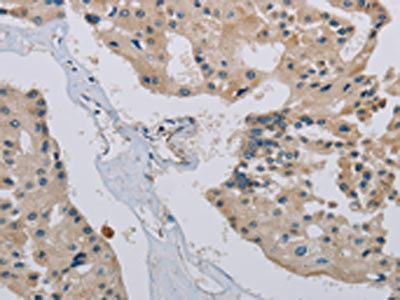

The image on the left is immunohistochemistry of paraffin-embedded Human prostate cancer tissue using CSB-PA152383(PHKA2 Antibody) at dilution 1/30, on the right is treated with synthetic peptide. (Original magnification: ×200)

The image on the left is immunohistochemistry of paraffin-embedded Human brain tissue using CSB-PA152383(PHKA2 Antibody) at dilution 1/30, on the right is treated with synthetic peptide. (Original magnification: ×200)